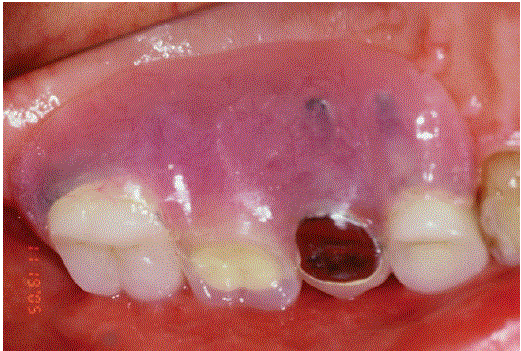

在根分离(#17)后(#17)构建左侧上颌部分CSC-套筒义齿单元(# 14 - #17)的磁性附着内冠(#15)(图1)。图2为部分CSCTD的横视图。带磁性附着体的CSCTD的颊侧和腭侧切面见图3和图4。图4为内冠(#14、#15、#17)的面部视图(图5)、右后视图(图6)和后颊面csc -望远外冠的外观(图7)。

图5:面部视图显示# 14,#15,# 17(2019)的金色内冠。

图6:颊面(右后)显示内冠(#14,#15)和3根分离#17。